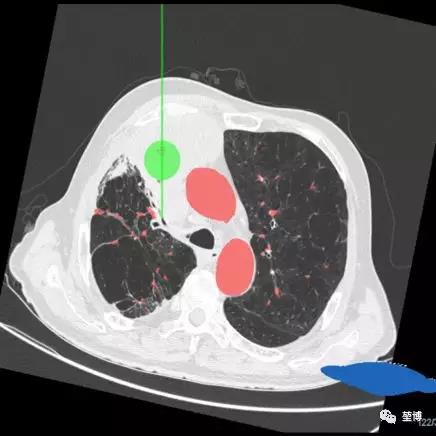

术前路径规划

一、气道内消融路径规划

二、气道外消融路径规划

POE穿刺点位于RB3

建立隧道直达病灶中心